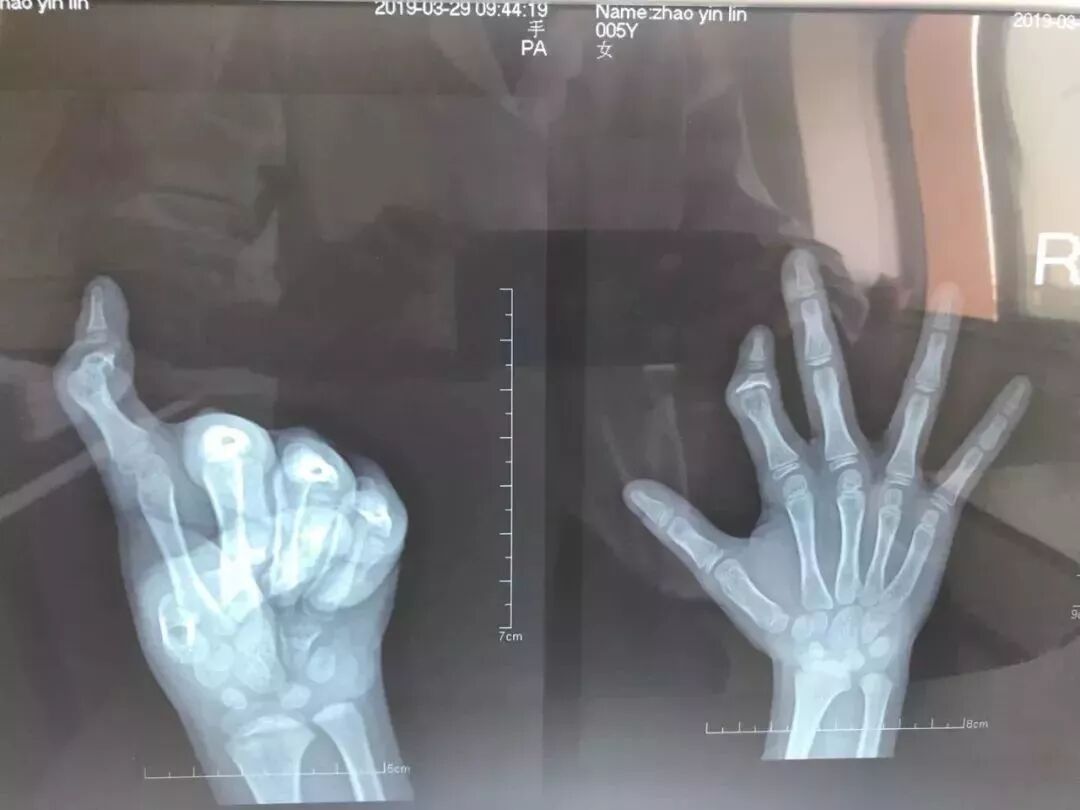

手外科医生罗鹏接待了这位远道而来的小姑娘,经过检查确诊琳琳是右手食指骨折并畸形愈合,认为可以分期进行手术矫正,同时告诉他们甘霖镇中心卫生院有这方面的专家,可以为他们进行手术治疗。台州医院兼恩泽医疗集团手足外科副主任郑有卯,每月第一、三个周六在医院坐诊、手术。

1月28日,三维CT结果出来以后,罗鹏医师将CT片传给了郑主任,郑主任阅片后回复:患儿患指关节畸形,中节指骨骨折并继续愈合,由于中间指骨骨垢被破坏,会严重影响骨骼发育,所以一期行患指关节畸形矫正,待3-6个月后二期行近节指骨延长术+患指功能重建术。